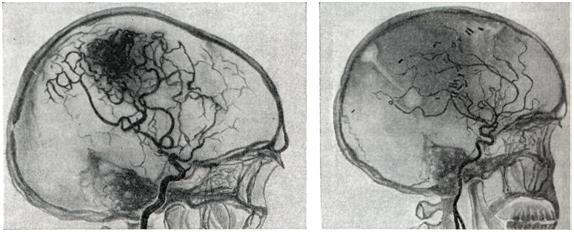

Рис. 4.

Ангиограмма больного после полного удаления большой артерио-венозной аневризмы теменной и задних отделов лобной доли (видны клипсы). Слева — ангиограмма больного до операции.

Радикальным методом лечения является полное иссечение артерио-венозной аневризмы (рис. 4). Однако при большой распространенности аневризм и их расположении в глубинных, жизненно важных структурах мозга такая операция может оказаться невыполнимой.